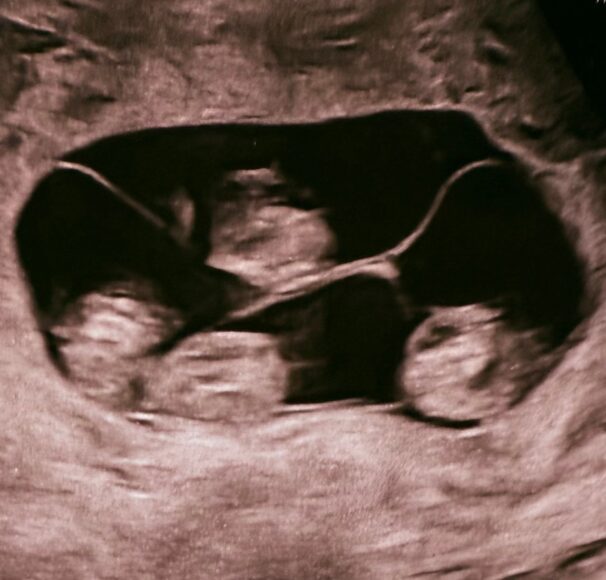

В петербургском роддоме – впервые в России – приняли однояйцевую четверню. На свет появились четыре сестренки

Уникальные роды прошли 2 апреля в Санкт-Петербурге: женщина произвела на свет четверняшек – девочек, развившихся из одной оплодотворенной яйцеклетки.

В роддоме №17 на Леснозаводской улице, где принимали роды, назвали это «чудом в четвертой степени». По статистике монохориальная (однояйцевая) четверня получается в одном случае на 15,5 миллиона родов. В России такой случай произошел впервые.

На свет появились, одна за другой, четыре очаровательных девочки. Их показатели, по оценке врачей, прекрасны для неполного срока, который они провели в материнской утробе: 1400 граммов и 38 сантиметров, 1570 г и 41 см, 1640 г и 41 см, 1360 г и 37 см.

Фото: vk.com/rdom17